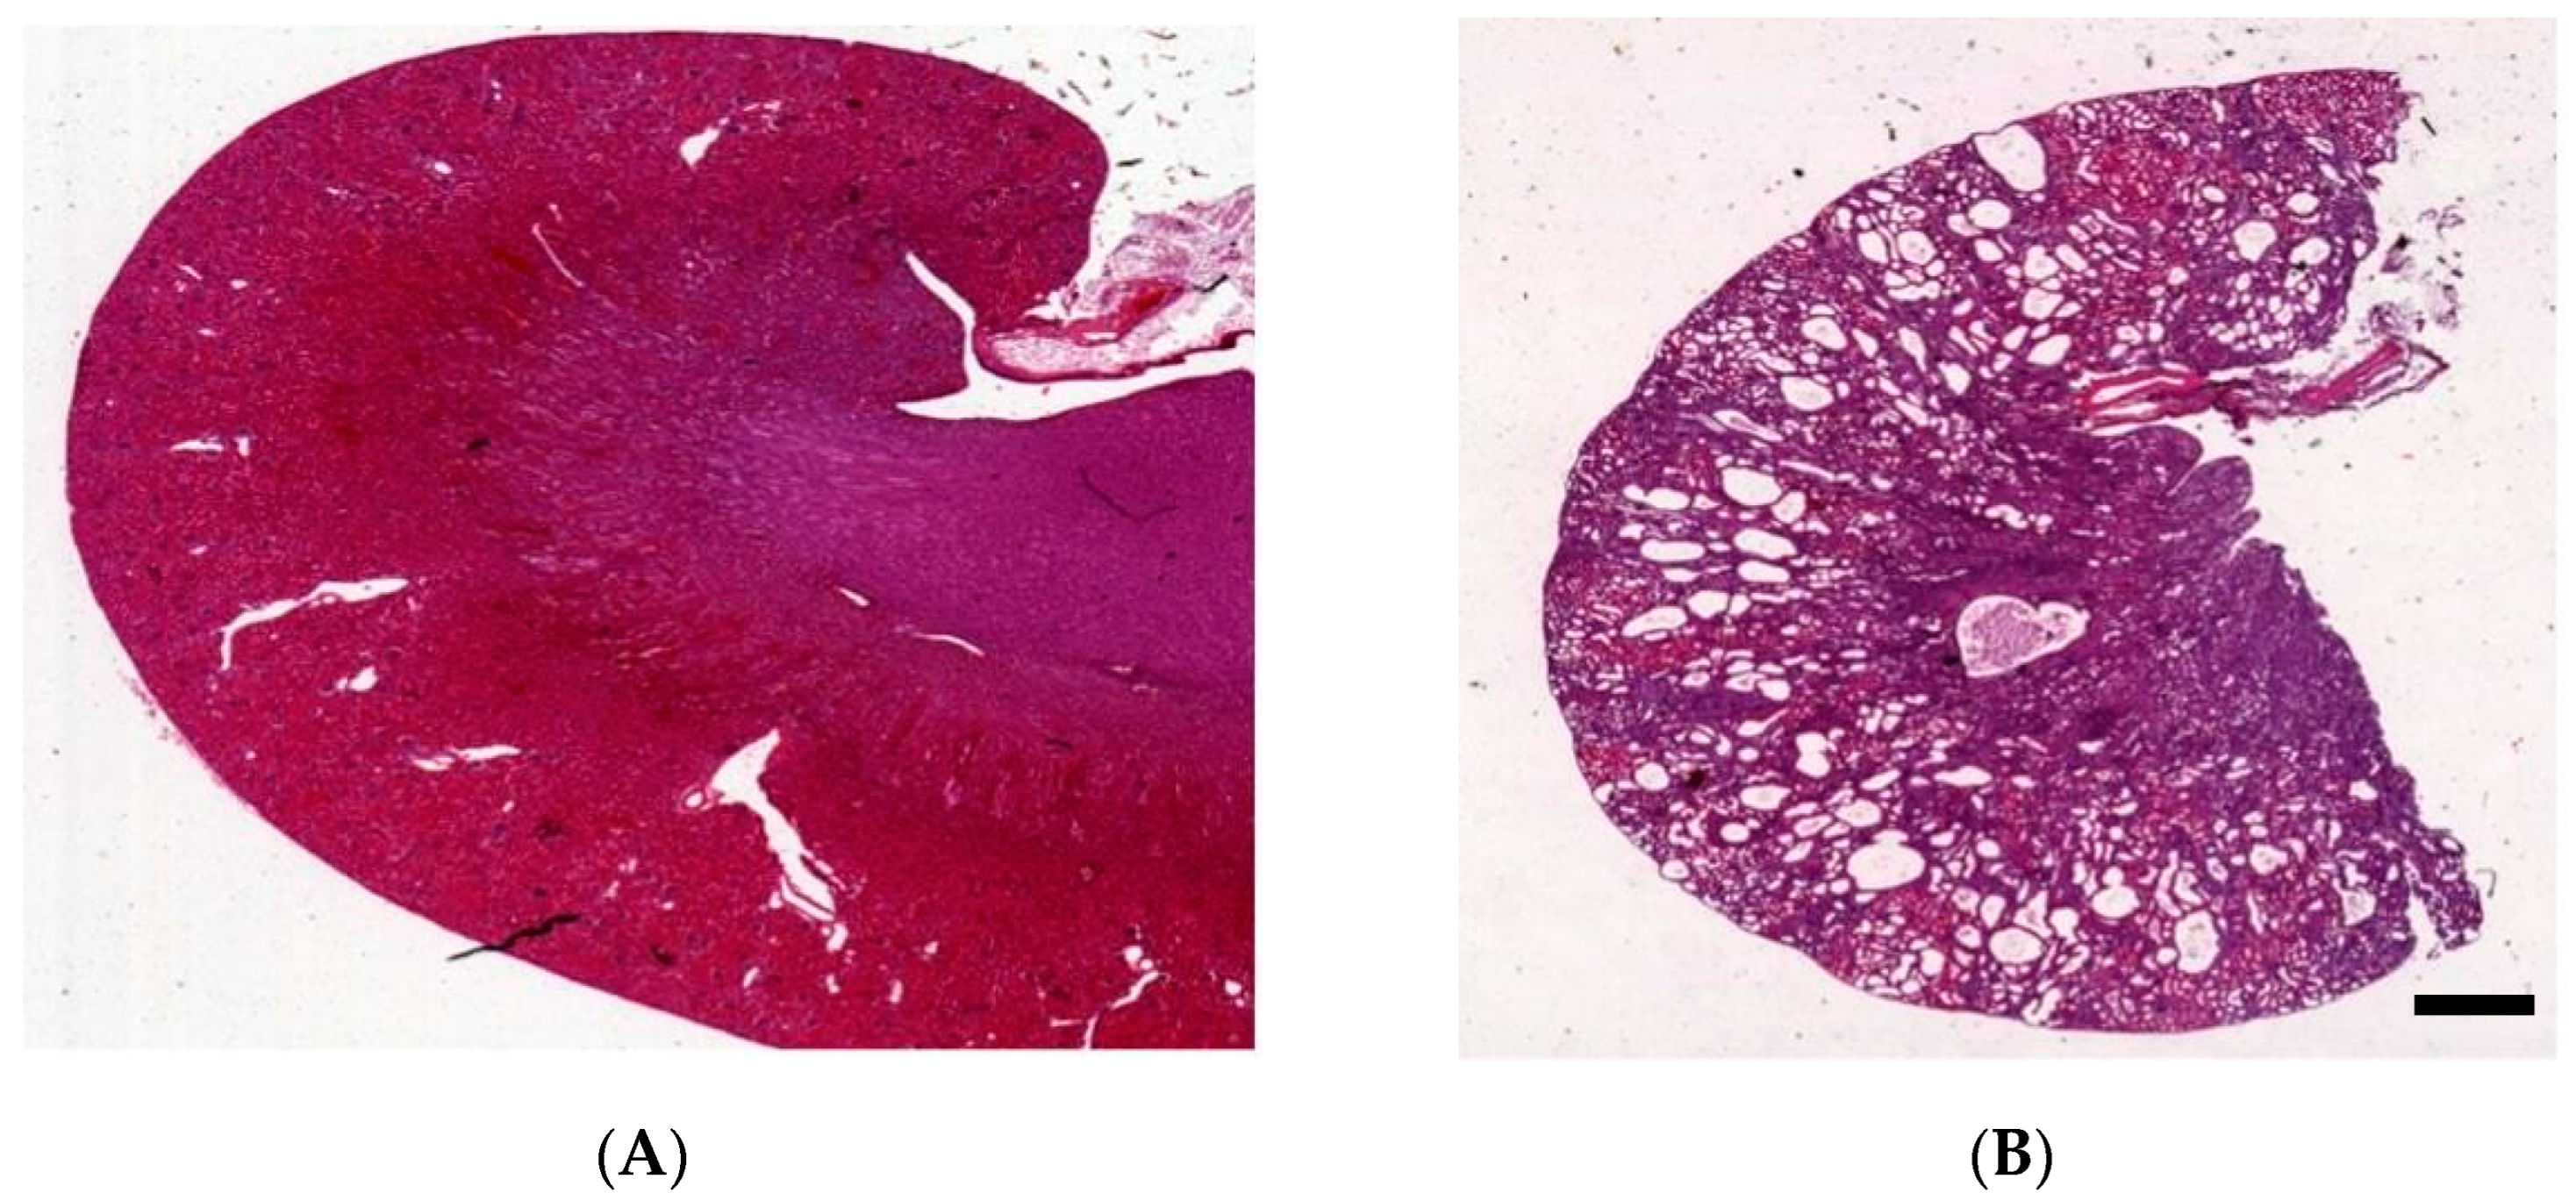

2. The Han:SPRD Rat Model

3. Kidney Histology of Han:SPRD Rats